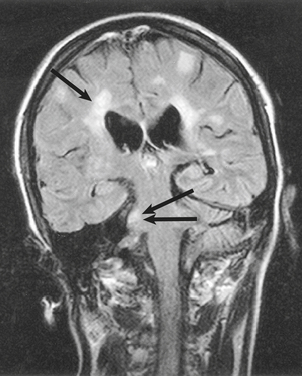

SYRINGOMYELIA

Syringomyelia is an uncommon condition in which a cavity (syrinx) develops within the spinal cord, sometimes extending up into the brainstem (syringobulbia). The cavity is usually situated in the central region of the cord, posterior to the central canal. Syringomyelia occurs most frequently in the cervical region of the cord, and usually extends for several centimetres in a vertical direction. However, extensive cavities involving almost the entire length of the cord have been described. Modern radiological techniques are of great value in delineating the extent of the lesion (see Fig. 26.22).